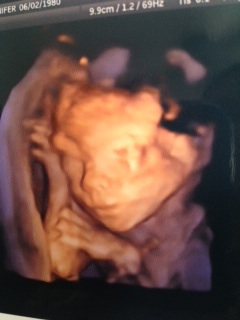

All complaints aside, the best thing so far is baby #2 is healthy and on-track with size. We have had no false positive genetic test scares, no amnio, no threatening of best rest, concerns about size of the baby, etc. Baby boy #2 is looking great! Below is a picture to prove it. Although, every time we mention “baby brother” to Emmy her response is “Baby sister. I said I want a baby sister”. She’ll come around sooner or later :)

Baby Brother